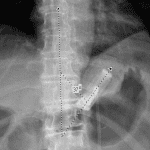

- O-shaped configuration of the gastric lap band

- Gastric lap band slippage

O-shaped configuration of the gastric lap band, concerning for slippage.

Nonobstructive bowel gas pattern.

Staghorn calculus in the right kidney.

No evidence of acute cardiopulmonary disease.